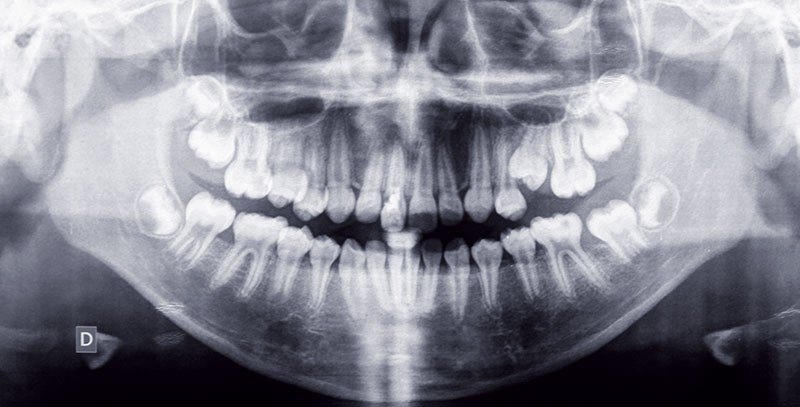

Traitement (fig. 10 à 25)

Un appareillage multi-attaches a été mis en place aux deux arcades. Un composite transitoire a été réalisé sur 11 afin de pouvoir la tracter à l’aide d’un bouton collé sur la face vestibulaire. Après la phase rapide d’alignement/nivellement un arc acier .018x.025 est inséré au maxillaire avec un step vertical en regard de 11 pour mettre en place les forces verticales d’extrusion. Des forces lourdes sont appliquées et réactivées tous les 15 jours afin d’obtenir ce mouvement. Une chirurgie mucco-gingivale…